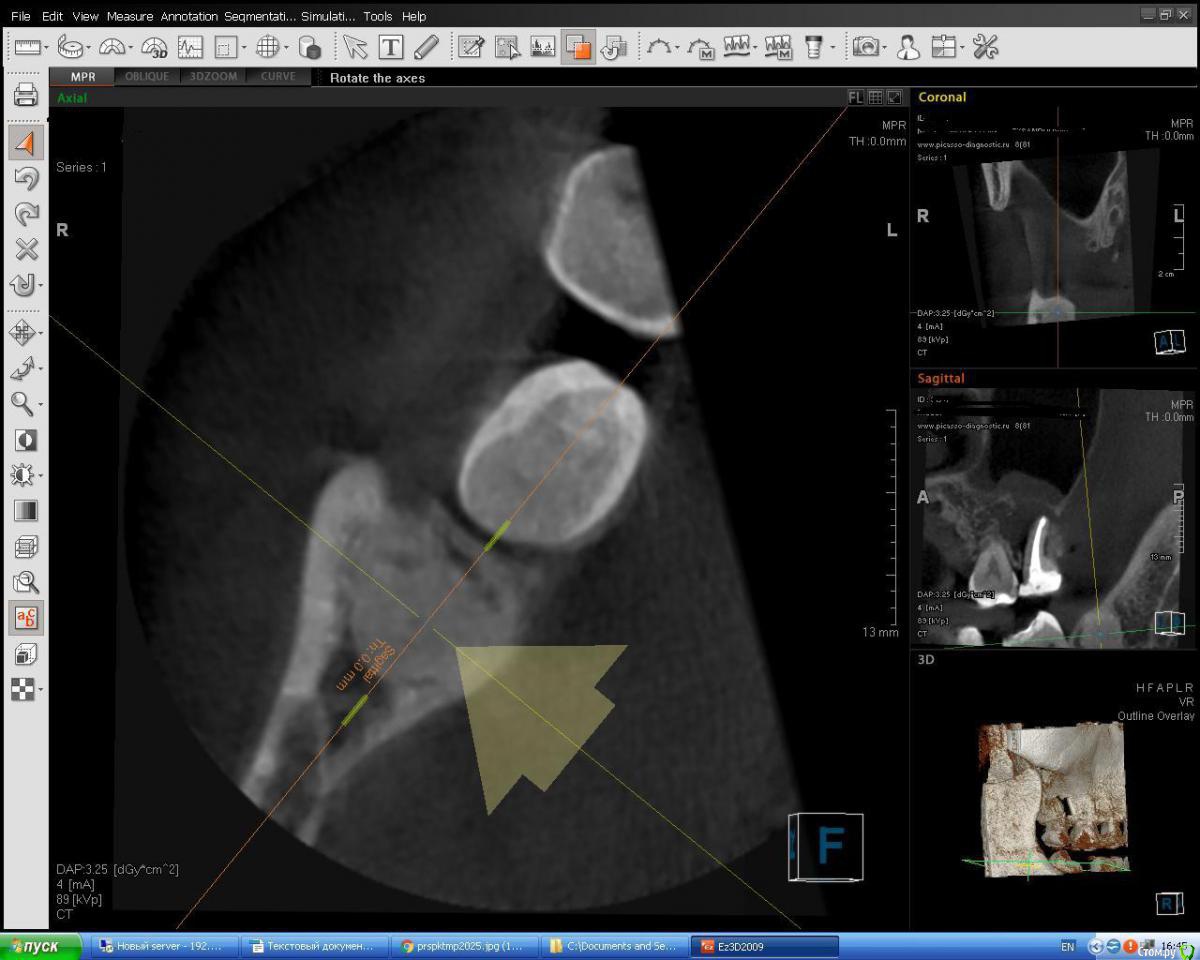

Jurai Опубликовано 12 ноября, 2015 Поделиться Опубликовано 12 ноября, 2015 (изменено) Смотрю КТ по другому поводу, случайно увидела вот это. Со слов пациентки, около года назад ей другой врач сказал, что это зуб новый растет. В полости рта - 47 отсутствует, 48 полностью прорезался, сдвинулся на место 47. Остеома? Изменено 12 ноября, 2015 пользователем Jurai Ссылка на комментарий

Alexey Doc Опубликовано 12 ноября, 2015 Поделиться Опубликовано 12 ноября, 2015 Очаг остеосклероза Ссылка на комментарий